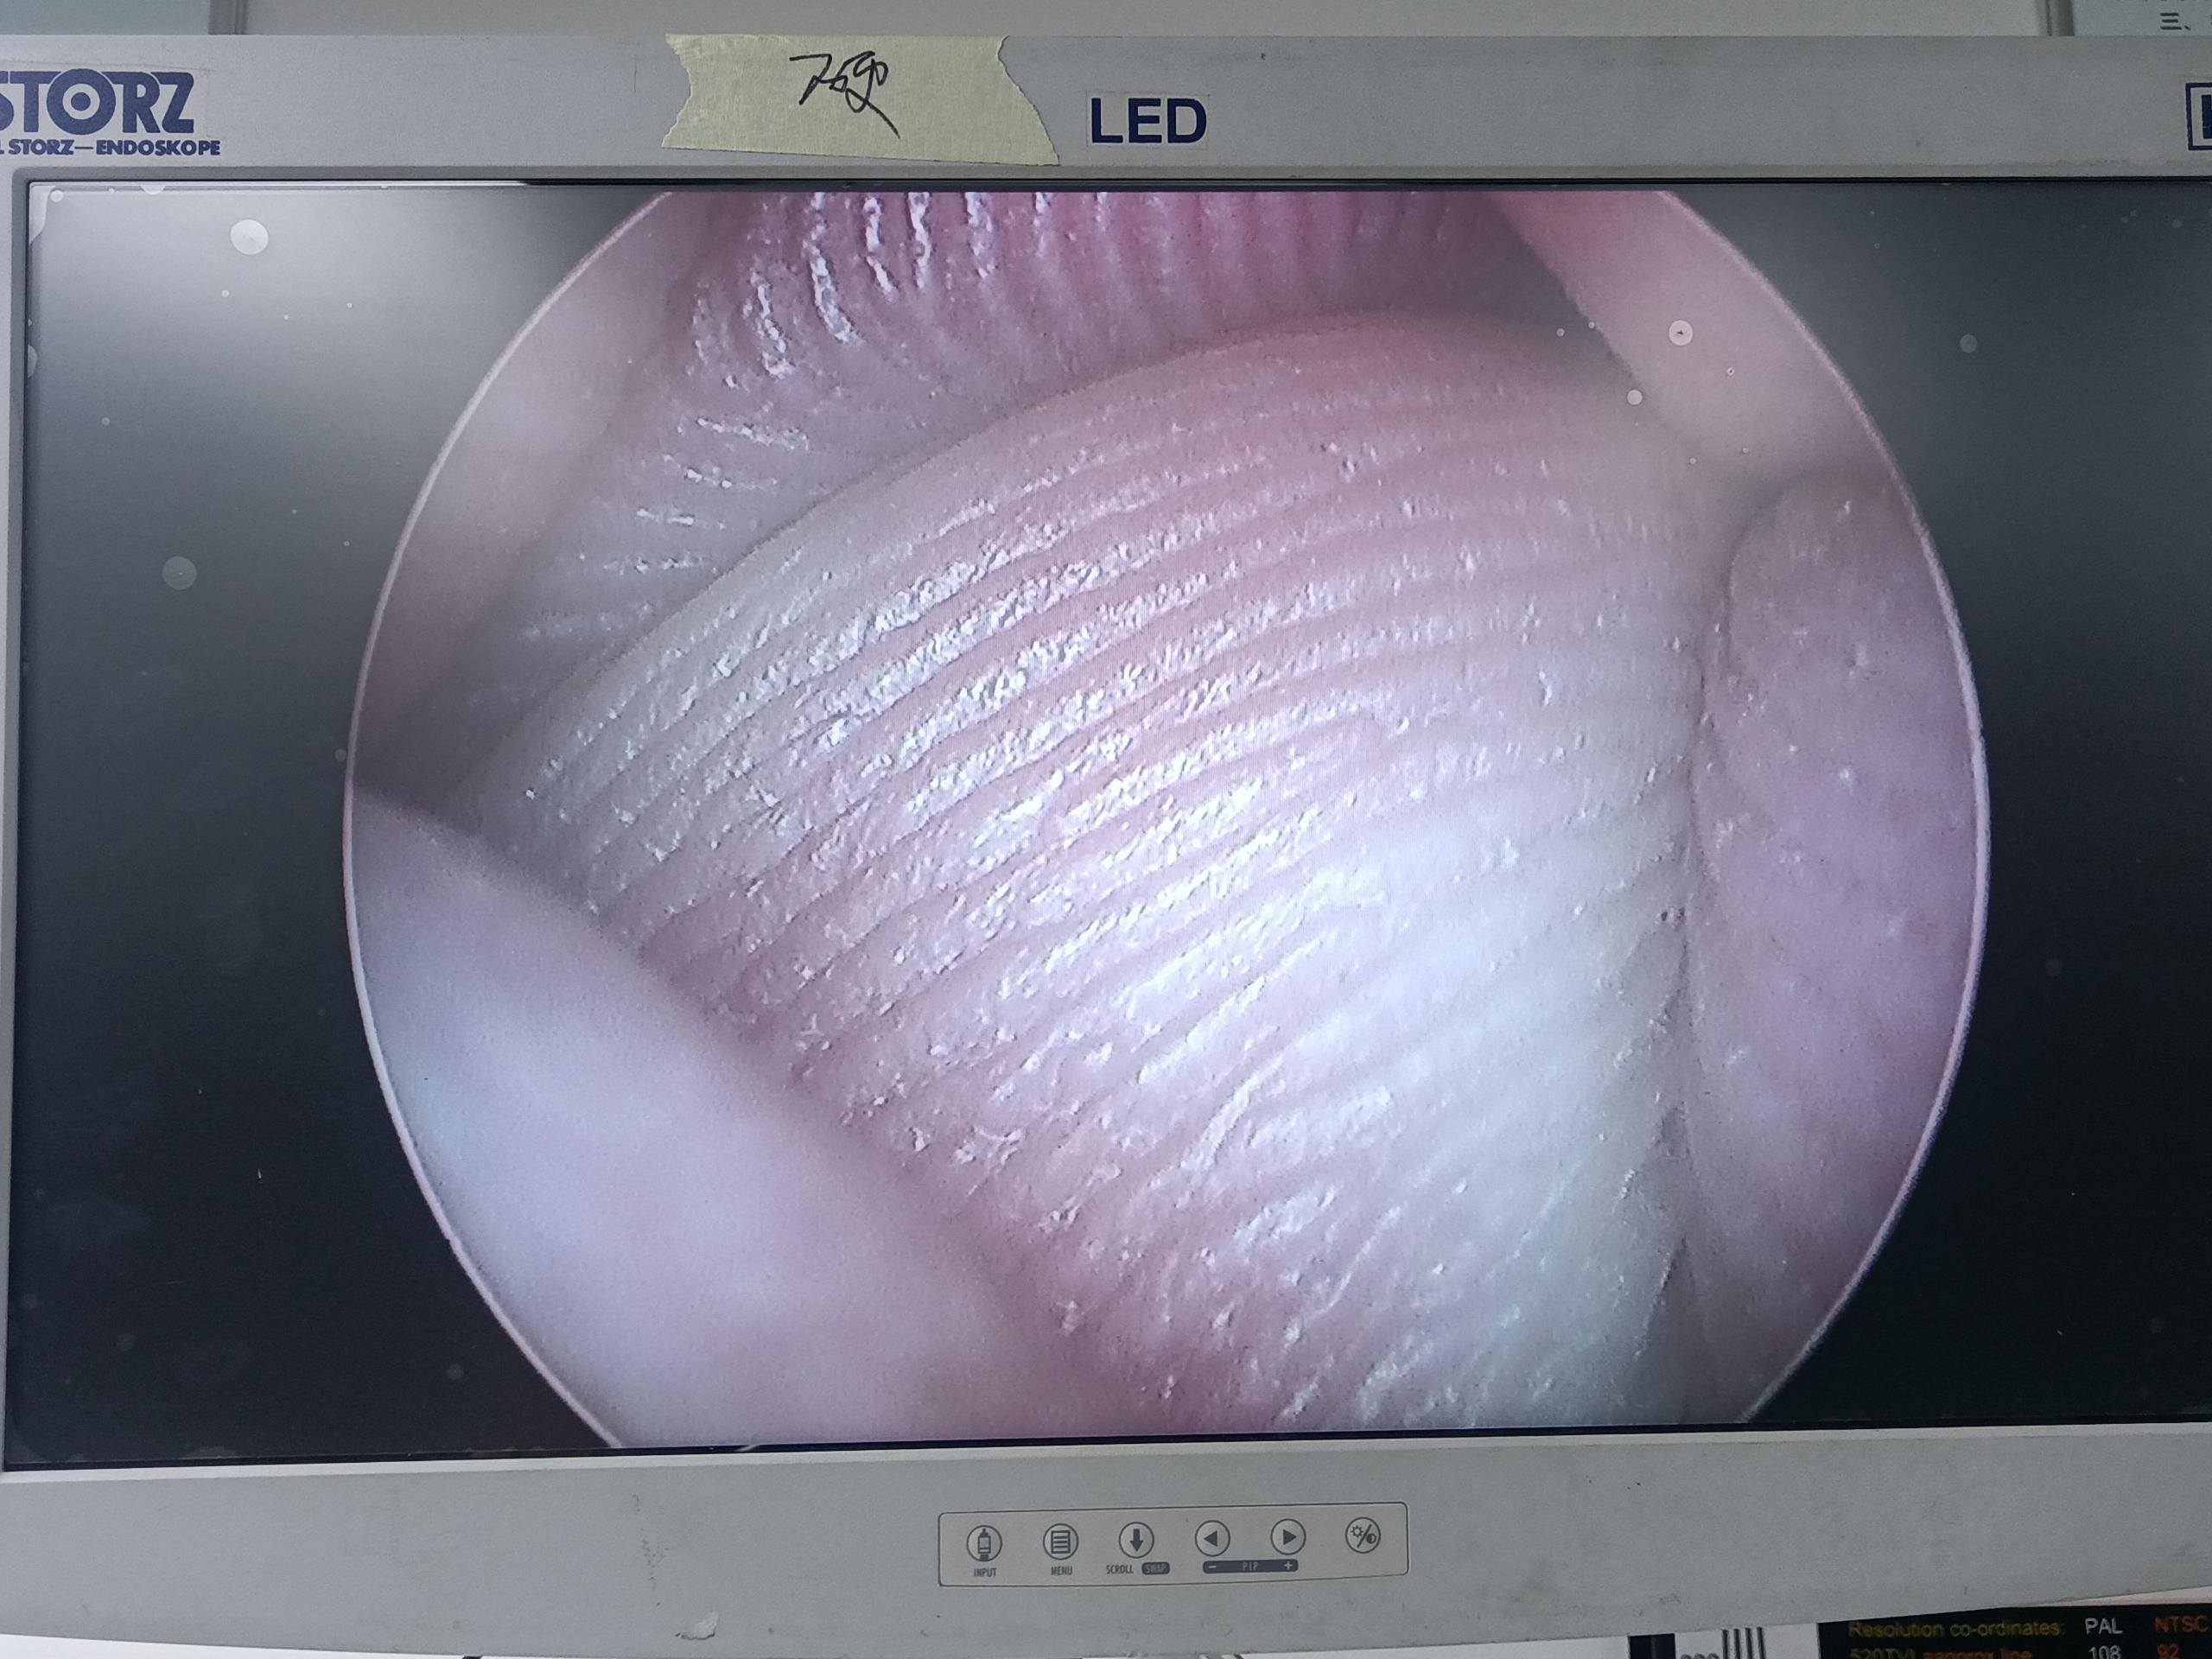

設備型號Wolf狼牌電切鏡8650.414

故障內容圖像模糊,棒透鏡破碎,導光錐破碎,目鏡罩破碎,鏡身有磕碰,但不影響使用。

維修方案更換棒透鏡、導光錐、目鏡罩,校對圖像,內窺鏡抗震蕩抗沖擊性能測試,內窺鏡密封性性能檢測;內窺鏡抗震蕩性能測試,內窺鏡冷熱沖擊性能檢測。